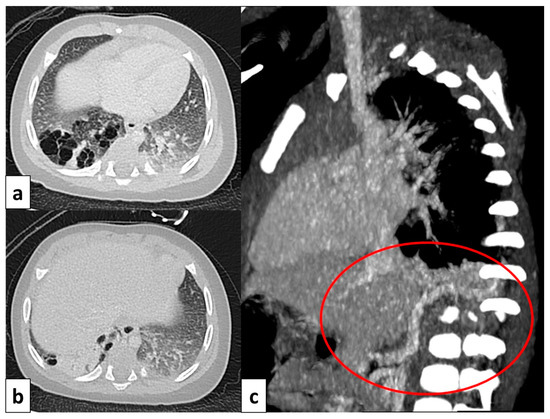

3.6.1. Pulmonary Sequestration